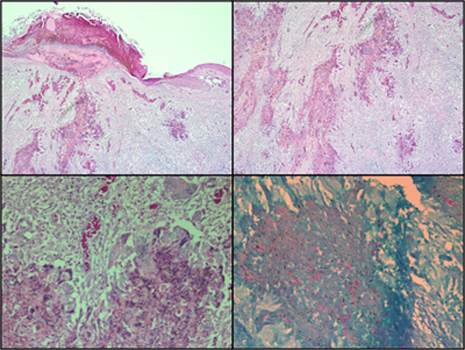

SKIN ASPERGILLOSIS. Tissue from a 30 days old broiler.

Description: Skin. The epidermis has multifocal ulcerations covered with serocellular crusts that contain bacterial microcolonies. The epidermal cells at the ulcers margins are hypertrophic. The dermis and subcutis are expanded with inflammation, multiple foci of necrotic cell debris, blood vessel congestion and edema. The inflammatory exudate contains primarily histiocytes and multinucleated giant cells (MNGC), lymphocytes, and some heterophils. Fungal hyphae with septa, parallel walls, and dichotomous branching are demonstrated by PAS stain within the necrotic material.

Morphologic Diagnosis: Sever, multifocal, ulcerative granulomatous dermatitis with intralesional fungal hyphae.

Disease Diagnosis: Skin Aspergillosis. Dr Z. Raviv